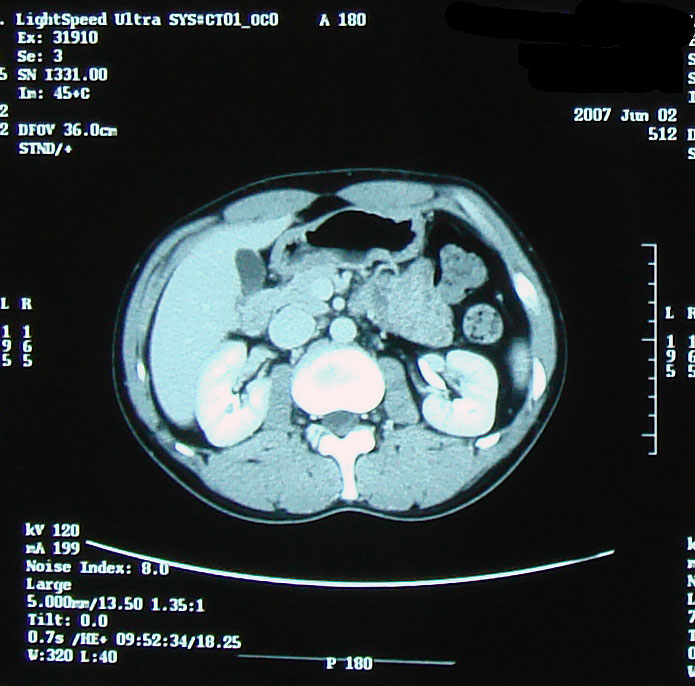

でも、髪質は脱毛前とは全く異なり、硬く、クセの強い、ゴワゴワしたものだった。 いろいろな人の体験記を読んでいたので、そうなるかもしれないこともわかっていたし、実際に抗癌剤治療をしたのだから「ま、そうだろうな」と思っていた。 でも、ここ最近ちょっと様子が変わったらしい。 今日、再び美容室に行った。 美容師さん:「少し柔らかくなったような・・以前はもっとこう・・何と言うか・・」 自分:「硬くてゴワゴワしてましたよね。」 少し髪質が柔らかくなってきたみたい。 いや、治療前の髪質に戻り始めたかな。 髪で風を感じるようになってきたのがちょっぴりうれしい最近です。 先日撮影したCT、採血結果を聞いてきました。 【画像】:変化なし 【HCGΒ】:0.1> 普通に仕事をして、普通に疲れてますが、検査的には問題なし。 この病気、わりと仕事現役世代が多いと思うのですが、みなさん治療後はバリバリ働いているのだろうか。 それで大丈夫なのだろうか。 それにしてもCT画像を見るのはおもしろい。 生きたまま自分の内部が見れるんだから。 毎回診察時に「写真撮っていいですか?」が恒例になってきてる。 先生も「あぁ、どうぞ(苦笑)。あ、撮るならこっちかな。」とか言って該当するほうのフィルムを移動してくれる(笑)。 そうだ、この日は入院時にお世話になった看護士の○澤さんが外来で助手をしてた。 ほとんど話ができなかったけど、この場をかりて 「大変お世話になりました。本当に感謝してます。」